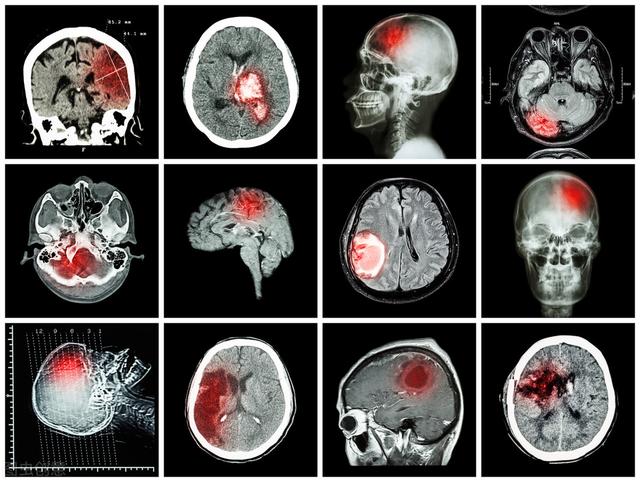

脳梗塞とは虚血性脳卒中の総称であり、脳組織の局所的な血液供給動脈の血流が急激に減少または停止することにより、脳組織の血液供給領域が虚血・低酸素状態に陥り、脳組織が壊死・軟化した状態であり、片麻痺、失語症、その他の神経障害など、対応する部位の臨床症状・徴候を伴う。

脳梗塞とは、脳血栓症、脳塞栓症、海綿状脳梗塞、一過性脳虚血発作など、脳血液供給の障害によって起こる脳病変で、脳卒中の約70%を占める。

脳梗塞発症後24〜48時間後に脳のCT検査を行うと、対応する部位に境界のはっきりしない低密度の病巣が認められ、何らかの占拠作用がある可能性がある。脳磁気共鳴(MRI)検査では、病変部のT1低信号と加重画像のT2高信号によって示される脳梗塞を早期に発見することができ、MRIはより小さな梗塞病変を検出することができる。

脳梗塞(虚血性脳卒中ともいう)とは、脳動脈がすべて狭窄・閉塞し、脳虚血・低酸素状態となり、脳組織が限定的に虚血壊死・軟化することをいう。 大血管の閉塞は大きな脳梗塞を引き起こし、片麻痺、脳ヘルニアの形成、昏睡に至ることもあり、重症例では死に直結することもある。

急性脳梗塞は、臨床的に非常によく見られる脳血管疾患で、死亡率や障害率が高い。ラクナ脳梗塞との違いは、主に閉塞した血管の大きさによるもので、通常脳梗塞と呼ばれるものは、頭蓋骨や脳の太い動脈の閉塞による脳組織の軟化や壊死も指す。